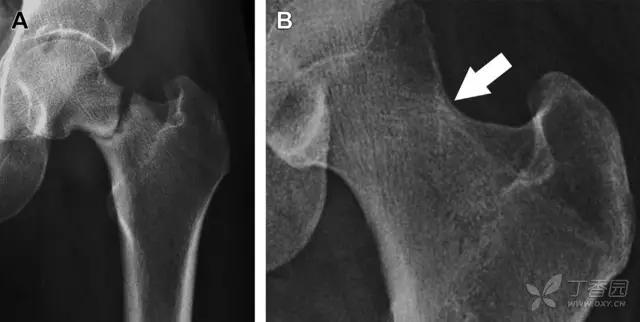

股骨颈应力性骨折

股骨颈应力性骨折在参加耐力运动的运动员中常见,且常发生在股骨颈压力侧。股骨颈基底部发现一垂直于骨皮质的线性硬化带可诊断这种类型的疲劳性骨折(图 8)。

图 8 长跑运动员股骨颈应力性骨折。X 片(A)和冠状位 CT 多维重建(B)图像示穿过股骨颈内侧皮质中的透亮区(箭头),周围硬化。骨折垂直于皮质

股骨颈张力侧的应力性骨折有可能发展为完全骨折(图 9)。

图 9 进食障碍患者股骨颈应力性骨折的张力侧。A 正位片示股骨颈完全骨折。B 2 周前的 X 片示局部骨量减少,正是后来发生骨折的位置(箭头)